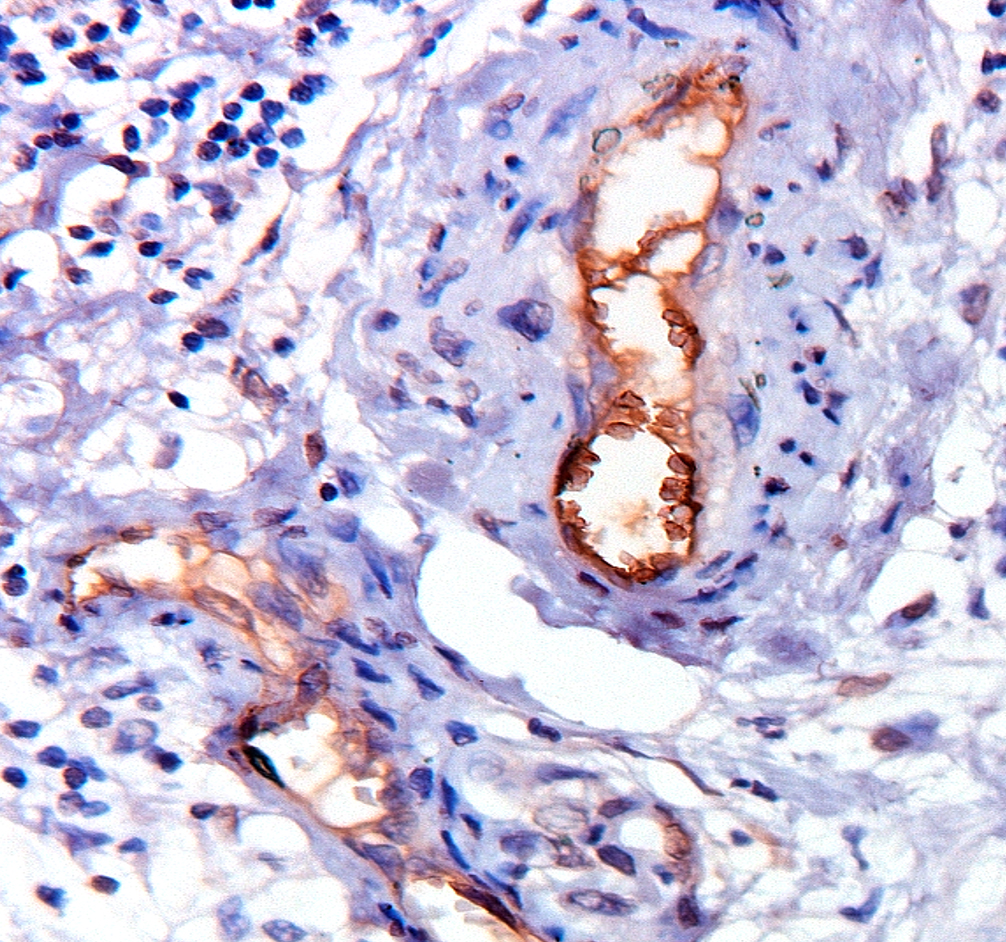

Coloration immunohistochimique du récepteur de l'insuline (INSR) dans une section microscopique du cancer de l'estomac humain. Une surexpression claire de ce récepteur (en brun) est observée dans les tissus tumoraux, alors qu'elle est absente dans les tissus non cancéreux de l'estomac. La recherche démontre que la surexpression de l'INSR est associée à une augmentation de l'angiogenèse. Cette découverte suggère que le ciblage direct de l'INSR endothéliale, probablement plus efficace par le ciblage d'une seule isoforme (INSR-A), peut ouvrir la voie à une nouvelle stratégie thérapeutique.

Immunohistochemical staining for the insulin receptor (INSR) in a microscopic section of human stomach cancer. A clear overexpression of this receptor (brown) is seen in the tumor tissue, while this is absent in non-cancerous stomach tissues. The research demonstrates that overexpression of INSR is associated with increased angiogenesis. This finding suggests that direct targeting of endothelial INSR, supposedly most beneficial through targeting of only one isoform (INSR-A), may present an interesting treatment strategy.